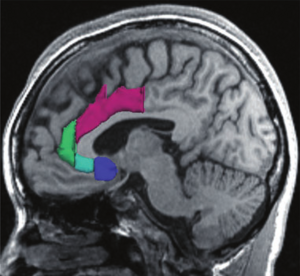

Treatment Planning and Delivery of Whole Brain Irradiation with Hippocampal Avoidance in Rats

Publication: PLoS One. 2015 Dec 4;10(12):e0143208. PMID: 26636762 | PDF Authors: Cramer CK, Yoon SW, Reinsvold M, Joo KM, Norris H, Hood RC, Adamson JD, Klein RC, Kirsch DG, Oldham M. Institution: Department of Radiation Oncology, Duke University Medical Center, Durham, NC, USA. Background/Purpose: Despite the clinical benefit of whole brain radiotherapy (WBRT), patients and physicians are concerned by the long-term impact on cognitive functioning. Many studies investigating the molecular and cellular impact of WBRT have used rodent models. However, there has not been a rodent protocol comparable to the recently reported Radiation Therapy Oncology Group (RTOG) protocol for WBRT with hippocampal avoidance (HA) which is intended to spare cognitive function. The aim of this study was to develop a hippocampal-sparing WBRT protocol in Wistar rats. Methods: The technical and clinical challenges encountered in hippocampal sparing during rat WBRT are substantial. Three key challenges were identified: hippocampal localization, treatment planning, and treatment localization. Hippocampal localization was achieved with sophisticated imaging techniques requiring deformable registration of a rat MRI atlas with a high resolution MRI followed by fusion via rigid registration to a CBCT. Treatment planning employed a Monte Carlo dose calculation in SmART-Plan and creation of 0.5 cm thick lead blocks custom-shaped to match DRR projections. Treatment localization necessitated the on-board image-guidance capability of the XRAD C225Cx micro-CT/micro-irradiator (Precision X-Ray). Treatment was accomplished with opposed lateral fields with 225 KVp X-rays at a current of 13mA filtered through 0.3 mm of copper using a 40x40 mm square collimator and the lead blocks. A single fraction of 4Gy was delivered (2Gy per lateral field) with a 41 second beam on time per field at a dose rate of 304.5 cGy/min. Dosimetric verification of hippocampal sparing was performed using radiochromic film. In vivo verification of HA was performed after delivery of a single 4Gy fraction either with or without HA using γ-H2Ax staining of tissue sections from the brain to quantify the amount of DNA damage in rats treated with HA, WBRT, or sham-irradiated (negative controls). Results: The mean dose delivered to radiochromic film beneath the hippocampal block was 0.52Gy compared to 3.93Gy without the block, indicating an 87% reduction in the dose delivered to the hippocampus. This difference was consistent with doses predicted by Monte Carlo dose calculation. The Dose Volume Histogram (DVH) generated via Monte Carlo simulation showed an underdose of the target volume (brain minus hippocampus) with 50% of the target volume receiving 100% of the prescription isodose as a result of the lateral blocking techniques sparing some midline thalamic and subcortical tissue. Staining of brain sections with anti-phospho-Histone H2A.X (reflecting double-strand DNA breaks) demonstrated that this treatment protocol limited radiation dose to the hippocampus in vivo. The mean signal intensity from γ-H2Ax staining in the cortex was not significantly different from the signal intensity in the cortex of rats treated with WBRT (5.40 v. 5.75, P = 0.32). In contrast, the signal intensity in the hippocampus of rats treated with HA was significantly lower than rats treated with WBRT (4.55 v. 6.93, P = 0.012). Conclusion: Despite the challenges of planning conformal treatments for small volumes in rodents, our dosimetric and in vivo data show that WBRT with HA is feasible in rats. This study provides a useful platform for further application and refinement of the technique. Funding:

MRI with labeled structures from atlas registered to the CBCT. Registration was carried out with the open source imaging tool 3D Slicer, Version 4.4.0. |